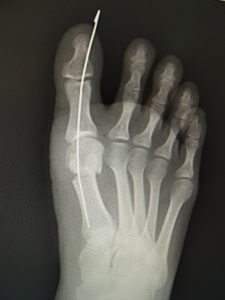

手術前 手術後4年

最近では、原則として固定ワイヤーは経皮的の一本のみとし、ワイヤーの先端は皮膚の外に出ているので、抜く時(術後3週間目)の患者さんの負担はほぼありません。こうすることによるデメリットはなく、むしろ術後成績は良くなっています。

手術前 手術後

真田理事長による手術の様子。外反母趾|症例 (左から 手術前、手術後、ワイヤ抜去後)